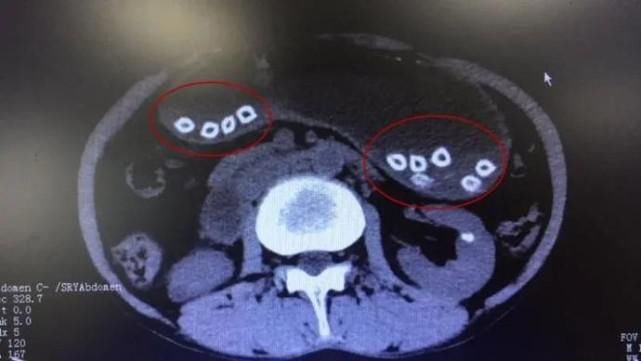

△CT结果显示的杨梅核

完善术前检查后,张渝为谢先生在胃镜下实施异物取出术,通过异物网篮共取出32颗杨梅核,其中有3颗杨梅核位于十二指肠球部,使得肠壁变薄,有穿孔的危险。术后,谢先生恢复良好。